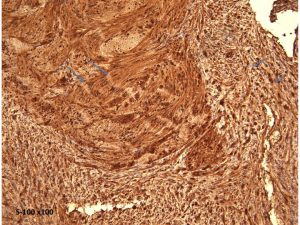

腫瘍細胞はS-100蛋白の免疫染色で陽性を示します。細胞密度が高くnuclear palisadingを示すAntoni type Aの部位(長い矢印)と細胞が比較的粗に配列するAntoni type Bの部位(短い矢印)でも陽性となります。S-100 x100.